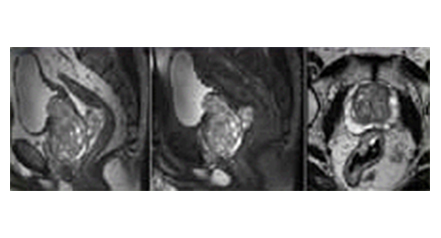

• 전립선/자궁 자기공명 영상(Prostate/Cervix Image) 이미지

전립선/자궁 자기공명 영상

(Prostate/Cervix Image)

특수한 영상 기법을 이용하여 전립선 암(prostate cander)이나 여성들의 자궁암(cervix caner)등을 진단하는데에 있어서 매우 탁월한 정보를 제공합니다.